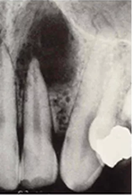

Infecțiile de la vârfurile rădăcinilor sunt reprezentate de zone în principal rotunde gri sau negre. Dacă aceste zone sunt mai mari și mai bine conturate, atunci diagnosticul se îndreaptă către un chist sau un granulom apical.

Chistul sau granulomul de mari dimensiuni apare ca o zonă gri intens spre negru care are o rădăcină de dinte ca punct de plecare după care se întinde în zonă; nu trebuie confundat cu zona nasului, sinusurile maxilare sau găurile mentoniere inferioare, care sunt formațiuni normale.